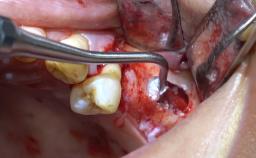

Module 3: Lateral Window Technique

Lateral Sinus Floor Elevation

Learning Module

Sinus Floor Elevation with Lateral Window Technique

Clinical Case Video

Implant Placement with Simultaneous Sinus Floor Elevation (Lateral Window Technique)